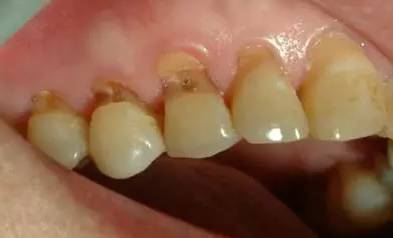

横向刷牙的习惯,是牙齿一颗颗掉了的“罪魁祸首”。医生表示,横着刷牙特别是横着使劲刷牙,时间长了,易造成牙齿颈部的楔状缺损损害,牙齿表面刷出一道道槽沟,进而形成牙髓炎、牙疼、牙变色、牙变死等。此外,酸、细菌、挤压的作用,也会造成牙齿“楔状缺损”。

症状较轻者:

对于组织缺损较少且无酸痛症状者,局部不需要特殊处理。但要避免横刷,并选用较软的牙刷和磨料较细的牙膏。

缺损较重者:

可选用与牙齿颜色近似又有一定粘接性的复合树脂或者玻璃离子粘固粉等将楔状缺损补好,以防继续发展。

重度缺损者:

重度缺损而引起牙髓炎、根尖炎的患者,要及时进行治疗。对于牙折者,根面好的行根管治疗后,作接冠术、桩冠或拔牙。